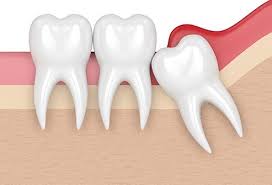

사랑니는 치아 중 가장 나중에 나고 자라므로 턱뼈에 공간이 부족하면 똑바로 나오지 못하고 주변의 잇몸을 괴롭히면서 통증을 유발한다고 한다.

▶사랑니가 똑바로 나지 않고 비스듬히 난 경우 ▶사랑니 주변 잇몸이 자꾸 붓고 아픈 경우 ▶사랑니와 그 앞 어금니 사이에 음식물이 자주 끼는 경우 ▶사랑니에 충치가 생겼으나 치료가 어려운 경우 ▶사랑니 앞의 어금니를 치료해야 하는데 사랑니로 인해 정상적인 치료가 어려운 경우 ▶교정치료를 해야 하는데 사랑니가 방해가 되는 경우 ▶X선 검사 소견 상 사랑니 주변에 혹으로 의심할 만한 부분이 나타난 경우 사랑니를 반드시 빼야 한다고 한다.